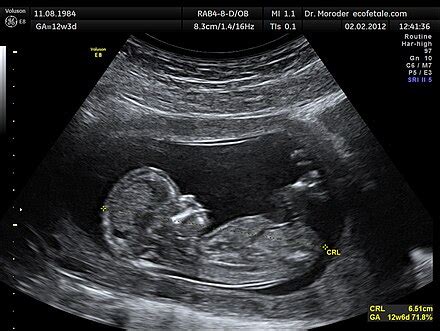

A terhesség alatt a magzat fejlődését ultrahangvizsgálatokkal kísérik figyelemmel. Ezek során mérik többek között a magzat fejátmérőjét (HC - fejkörfogat, BPD - koponya harántátmérő), haskörfogatát (AC) és combcsont hosszát (FL). Ezek az értékek segítenek megbecsülni a magzat súlyát (EFW - becsült magzati súly) és fejlettségét.

Ultrahangvizsgálat a 40. héten